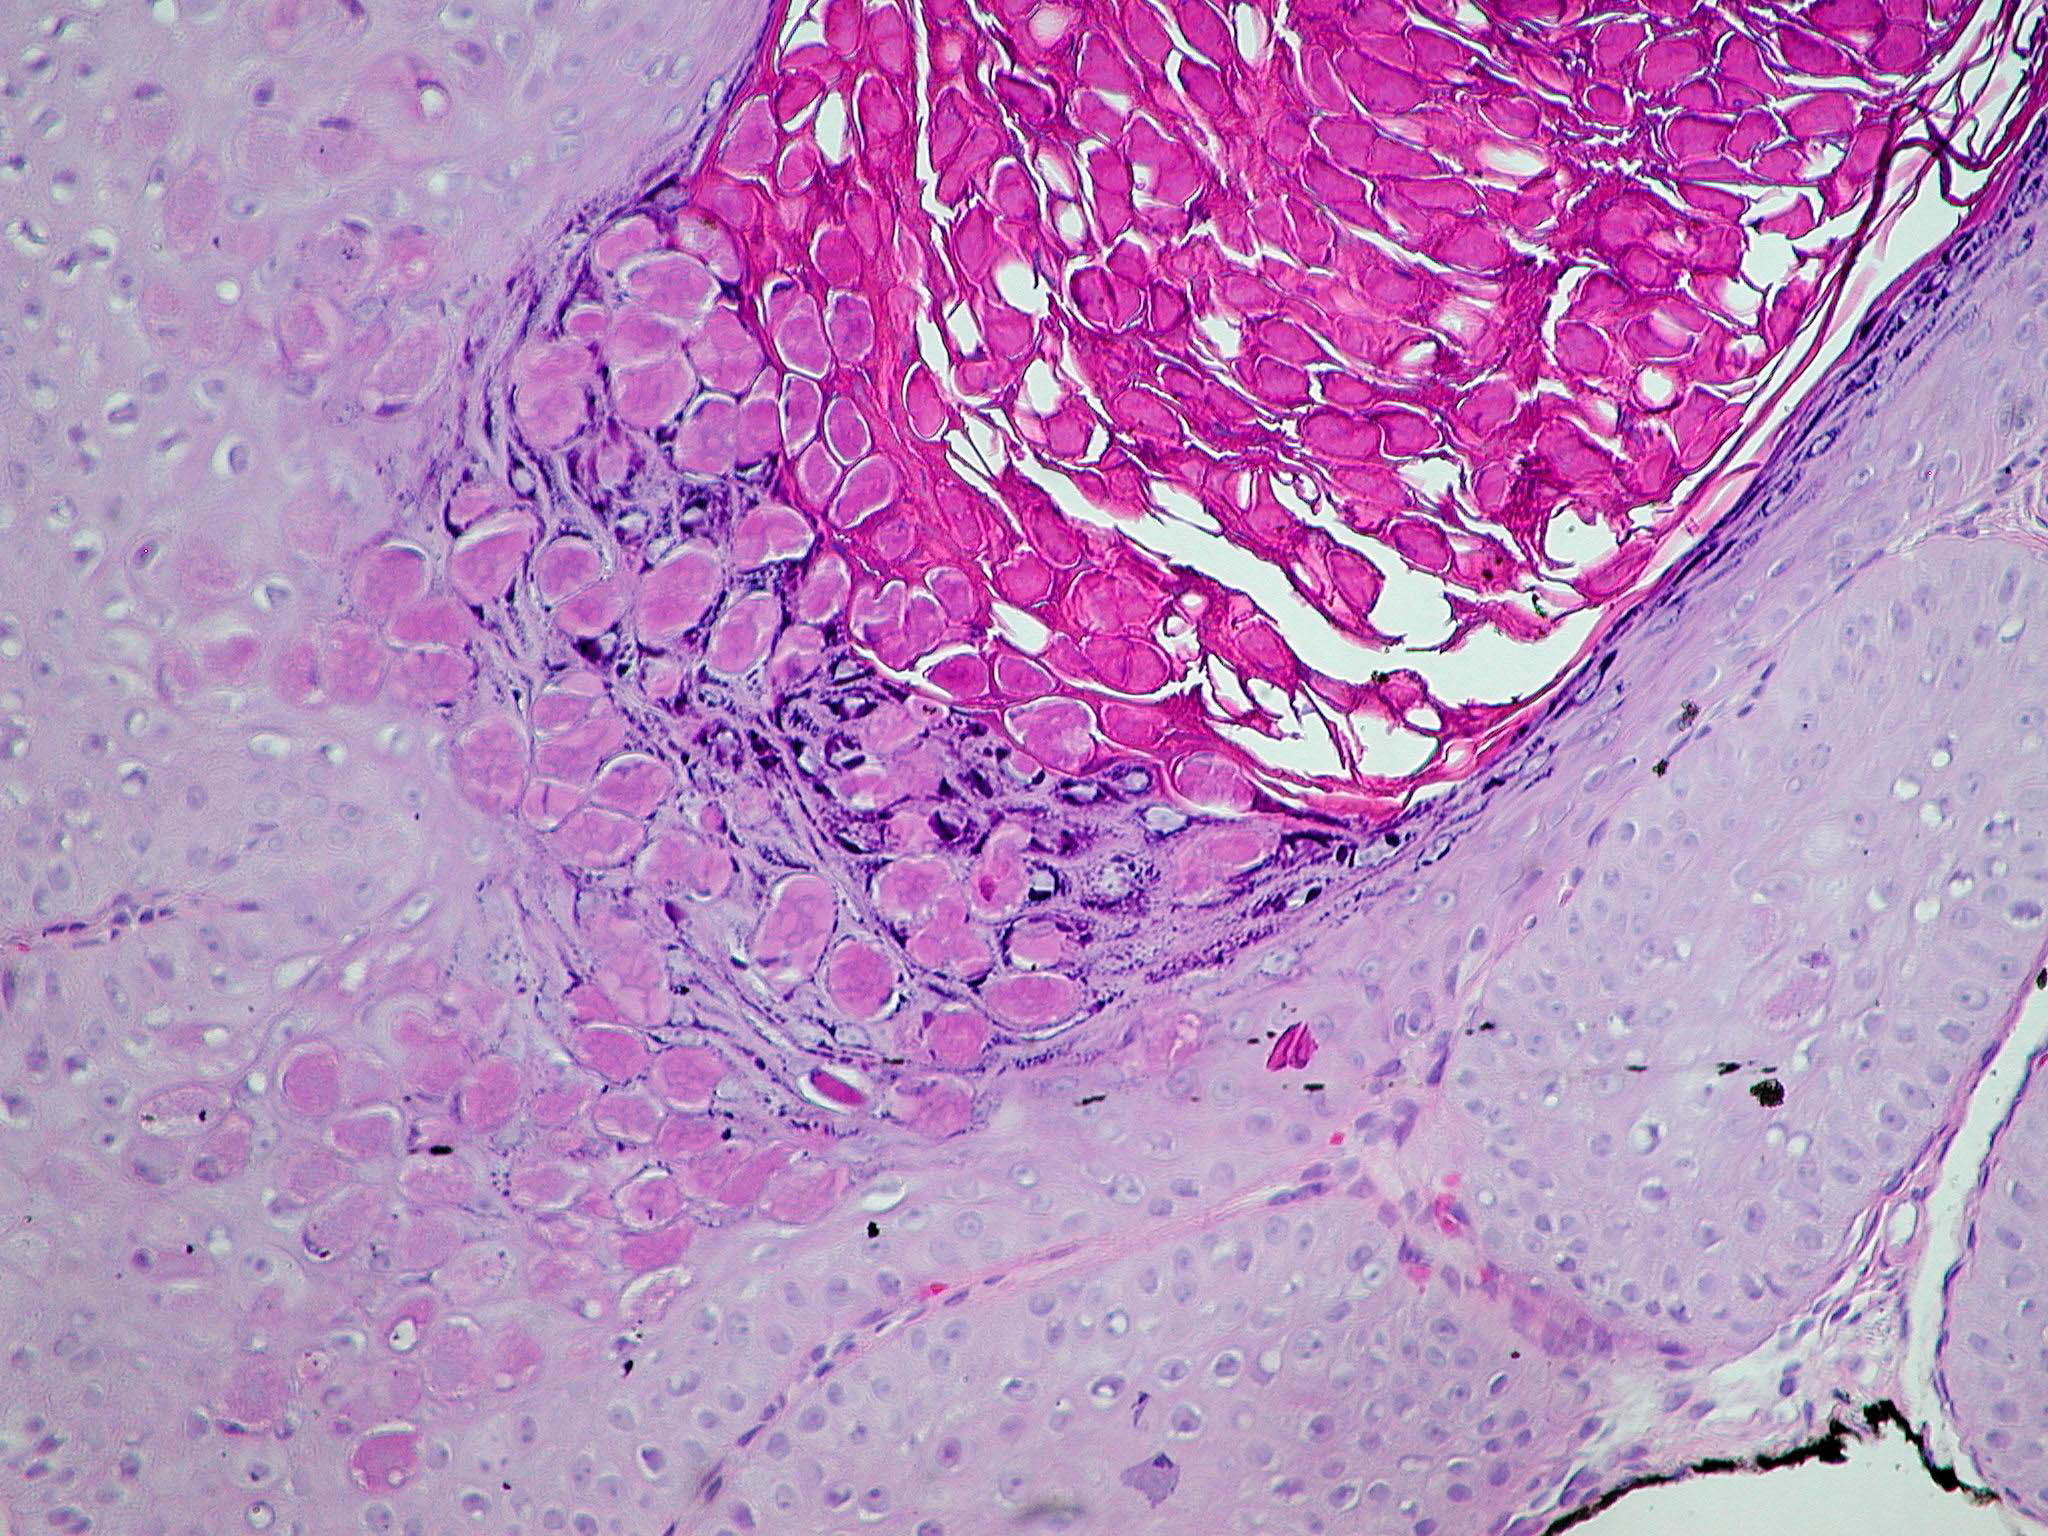

molluscum-contagiosum